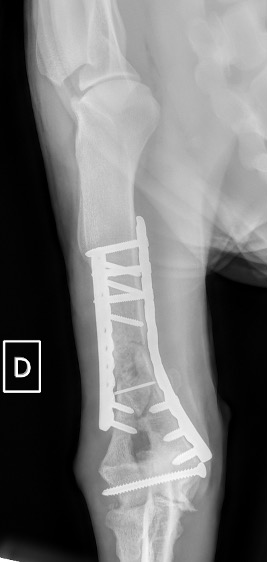

Notre préférence va vers le placement de deux plaques humérales : une médiale de la plus grande taille possible et l’autre latérale, généralement d’une taille inférieure à la première. Dans l’exemple 1 (chat européen), une plaque de 2 mm est utilisée médialement et une plaque de 1,5 mm latéralement. Dans l’exemple 2 (chien Malinois), une plaque de 3,5 mm est utilisée médialement et une plaque de 2,7 mm latéralement.

Exemple 2 :

Figure 5 : Post-Op Immédiat